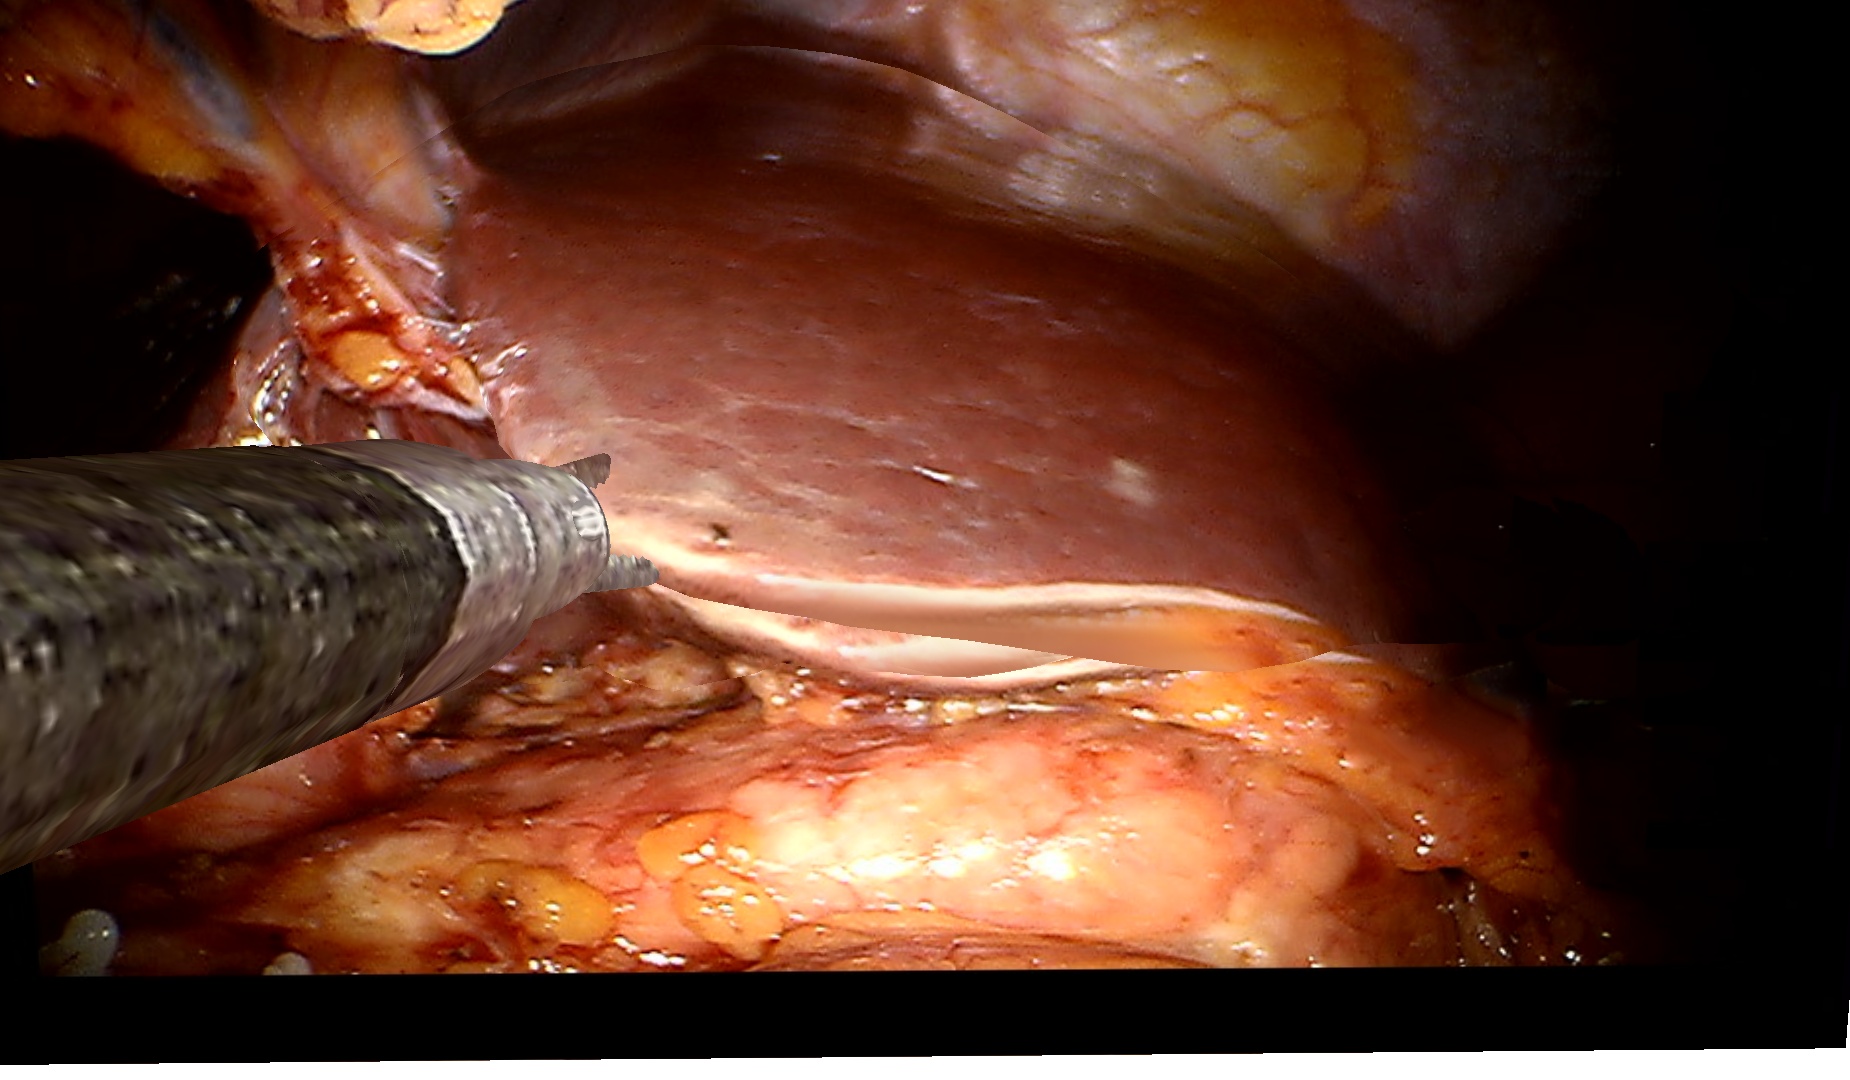

To demonstrate the effectiveness of our method on clinical data, we use a dataset of two visceral pig surgeries with a preoperative post-insufflation CT, initial rigid registration, a tracked laparoscope, and corresponding 2D monocular RGB videos. Surgical tools were masked out using SurgicalSAM [23]. The first sequence from the first surgery shows a tool-tissue interaction, whereas the second one shows a breathing motion without external manipulation. Because there is no deformed ground truth, as measuring intraoperative deformation would require intraoperative scanning, we demonstrate qualitative results.

Figure˜4 shows results on the tool-tissue interaction. The surgical tool presses down on the stomach, leading to the deformations tracked in the deformed mesh and CT (bottom rows). Although the difference in pressure applied between B and C appears marginal, we successfully track the increasing deformation, the difference being visible in both mesh and CT. For D and E, the tool is repositioned, now pulling the stomach back. Note how this backward pull is visible in the respective deformed CTs by a deformation to the right, since the laparoscope captures the scene roughly in the coronal plane, whereas the CT slice is shown in the sagittal plane.

Refer to caption

Figure 4: Examples from a tool-tissue interaction sequence. Rows from top to bottom: input images acquired by the laparoscope, images rendered with our method, deforming mesh, and deforming CT. Arrows in A point to the deforming anatomical structure, circles in B highlight the area of deformation, and arrows in E visualize the pull direction. See video in the supplementary material.

Since we rely on an initial registration, we are also subject to registration errors. There is a slight misalignment between the structure being manipulated in the input images (stomach) and the deforming mesh. Also note that we initialize our mesh from a post-insufflation CT, ensuring that the initial mesh and the intraoperative state early in surgery are still very similar. Regarding the deformation of the CT, we can only capture surface deformations by deforming our mesh. A more realistic deformation of deeper layers would require biomechanical modeling. Apart from those caveats, the method does not work in real time yet. Given the strides being made in the 3D computer vision community around 4DGS, we are confident that this problem will be solved soon. Despite those limitations, the deformations of the stomach in the CT are sensible and correspond to the tool-tissue interaction as confirmed by a board-certified surgeon.